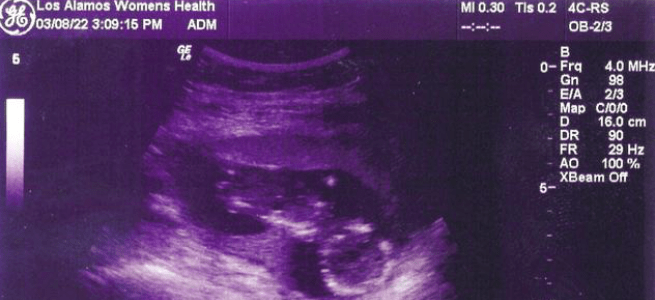

A daughter, Sophie — A legacy.